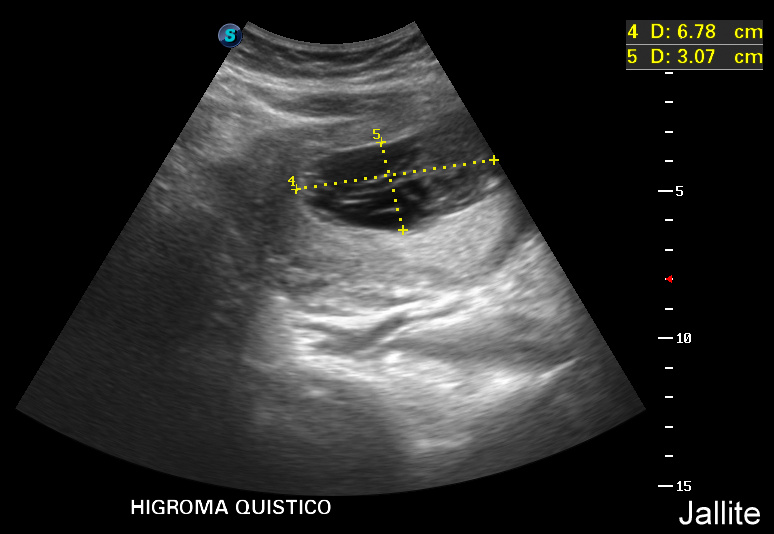

Recurrence: Isolated or part of Turner syndrome: no increased risk of recurrence. Part of autosomal recessive syndroms: 25%. The Fetal Medicine Foundation is a Registered Charity that aims to improve the health of pregnant women and their babies through research and training in fetal medicine.. Resumen . Objetivos: Determinar la importancia del espacio retronucal en fetos entre las 11 y 13+6 semanas, identificando sus características, la asociación con anomalías cromosómicas y las posibles diferencias entre higroma quístico y translucencia nucal aumentada.Diseño: Estudio transversal prospectivo.Institución: Instituto Latinoamericano de salud Reproductiva, Lima, Perú.

Higroma Quistico

¿Cuál es la diferencia entre el higroma quístico y la translucencia nucal?

Higroma Quístico

Higroma Quistico

Ecografia 2D 11 semanas Higroma quistico pliegue nucal patologico Dr. Rafael Ortega Muñoz

HIGROMA QUISTICO MEDICINA FETAL PERÚ YouTube

Large cystic hygroma (arrows). First trimester ultrasound (12 weeks),… Download Scientific

Higroma Quistico

Higroma Quistico

Resolución espontánea del higroma quístico en un feto con síndrome de turner y evolución postnatal / Spontaneous resolution of cystichygroma in a fetus with turner syndrome and postnatal evolution. Results. The overall incidence of cystic hygroma was 1/1851 live newborns. The mean gestational age at diagnosis was 14.6 weeks and the mean maternal age at diagnosis was 29 years. Seventy percent of cystic hygromas had associated anomalies and 63% of the karyotypes studied were abnormal. Induced abortion was performed in 56%.